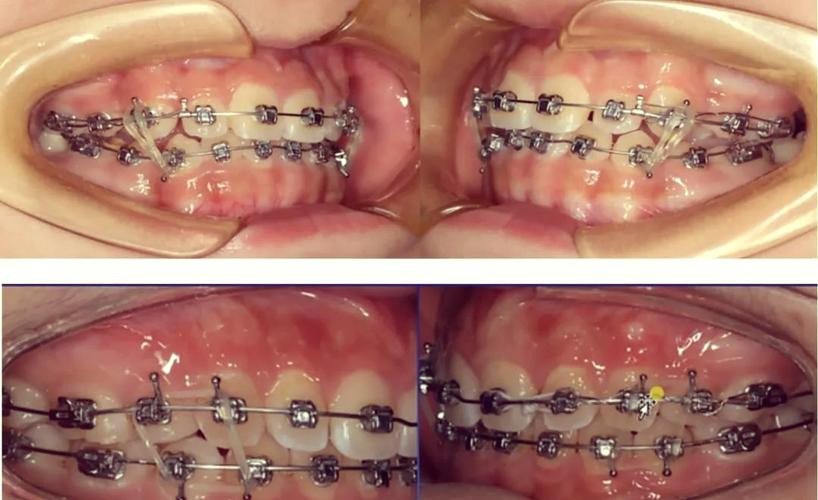

(图片来源网络,侵删)- 洗干净双手。

(图片来源网络,侵删)- 当橡皮圈两端都准确无误地套在了上下对应的挂钩上后,轻轻松开手指。

(图片来源网络,侵删)